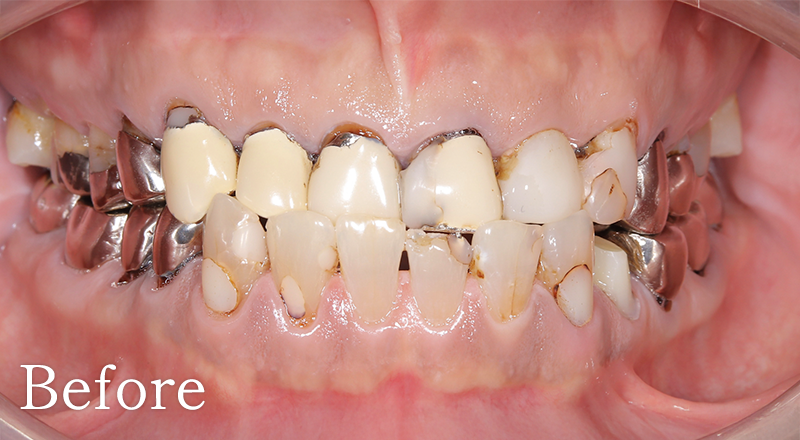

CASE4

骨格1級患者に対し、臼歯部にインプラント治療を行い咬合回復を行なった1症例

主訴 右側でうまく噛めない

治療内容 下顎臼歯部インプラント、咬合再構成、上顎矯正治療、セラミック治療

治療期間 約2年

費用 診断料:22万円(税込)

下顎顎臼歯部インプラント埋入手術:22万円(税込)×4本

セラミック補綴:22万円(税込)×4本

セラミック治療:11万円(税込)×9本

矯正治療:44万円(税込)